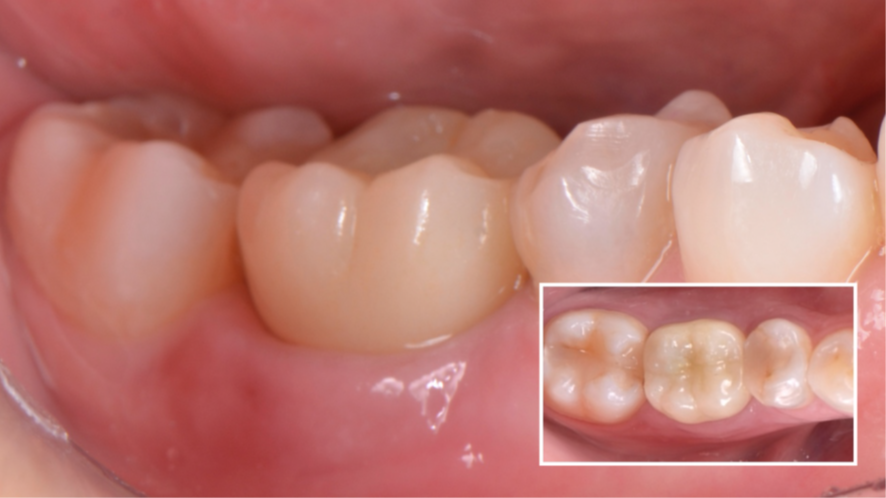

Aguardado 90 dias (Figura 11), o cicatrizador personalizado foi removido para avaliação do perfil de emergência (Figura 12) e da osseointegração do implante.

Partimos então para o escaneamento com o scanner Dexis IS3700 para realização da coroa sobre implante definitiva em zircônia. Fizemos a técnica do triplo escaneamento: 1- escaneamento do cicatrizador personalizado em boca (Figura 13); 2- escaneamento do transferente digital do CMAR (Figura 14); 3- escaneamento do cicatrizador personalizado fora da boca, parafusado no análogo (Figura 15).

Agora, o laboratório de prótese consegue alinhar as malhas e fazendo a subtração da malha referente ao escaneamento do cicatrizador personalizado fora da boca, parafusado no análogo, temos exatamente o perfil de emergência adquirido pelo cicatrizador personalizado. Então, é realizado o CAD da coroa sobre implante (Figura 16), e após a fresagem em zircônia, acabamento, polimento e maquiagem, recebemos a coroa fresada em zircônia cimentada no pilar Base T (Figuras 17 e 18) pronta para ser instalada no implante. Logo após a instalação da coroa sobre implante (Figura 19), uma radiografia periapical foi realizada (Figura 20), a fim de confirmar a adaptação correta da coroa sobre implante.